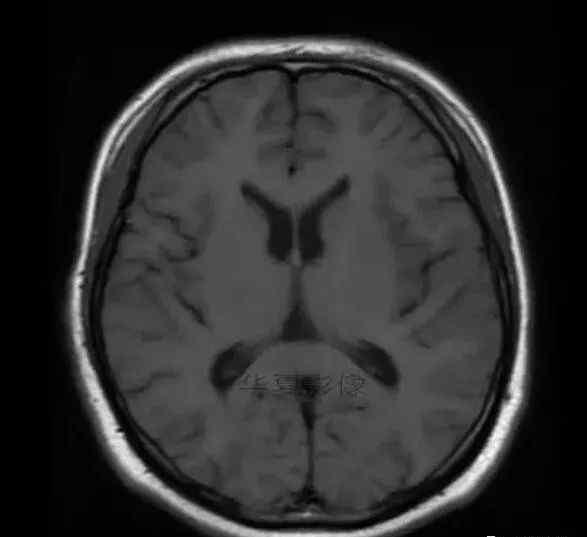

1.左侧颞叶、海马和岛叶T1WI信号低,T2WI信号高

2.病变没有明显的边界

3.占用效果不明显

4.豆状核不受影响